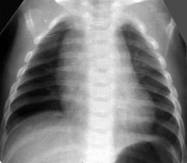

Умеренное снижение пневматизации легких, различимы воздушные бронхограммы, границы сердца чёткие (Рис.4).

Рисунок 4 Рентгенограмма грудной клетки в прямой проекции в горизонтальном положении. ( Диагностика и лечение РДС недоношенных // метод. Рекомендация, 2007)